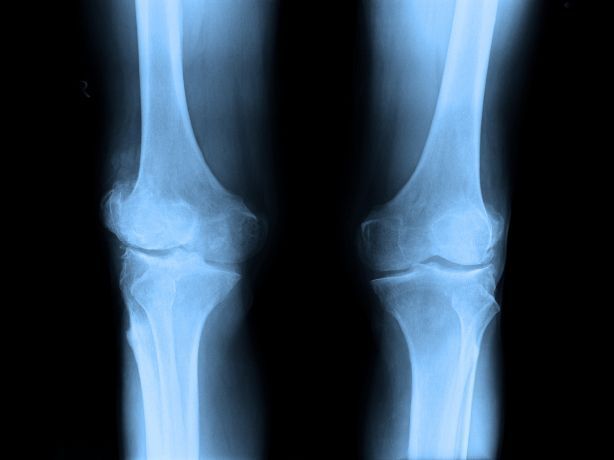

Teriparatide is used to treat osteoporosis (a condition in which the bones become thin and weak, hence brittle, and break easily) in women who have undergone menopause ('change in life,' end of menstrual periods), who are at high risk of fractures (broken bones), and cannot use other osteoporosis treatments.

It is also used to increase bone mass in men with certain types of osteoporosis who are at high risk for having broken bones (fractures), and who cannot use other osteoporosis treatments. Teriparatide injection is also used to treat osteoporosis in men and women who are taking corticosteroids (a type of medication that may cause osteoporosis in

some patients) who are at high risk of fractures (broken bones), and cannot use other osteoporosis treatments. Teriparatide injection contains a synthetic form of natural human hormone called parathyroid hormone (PTH). It works by causing the body to build new bone and by increasing bone strength and density (thickness).